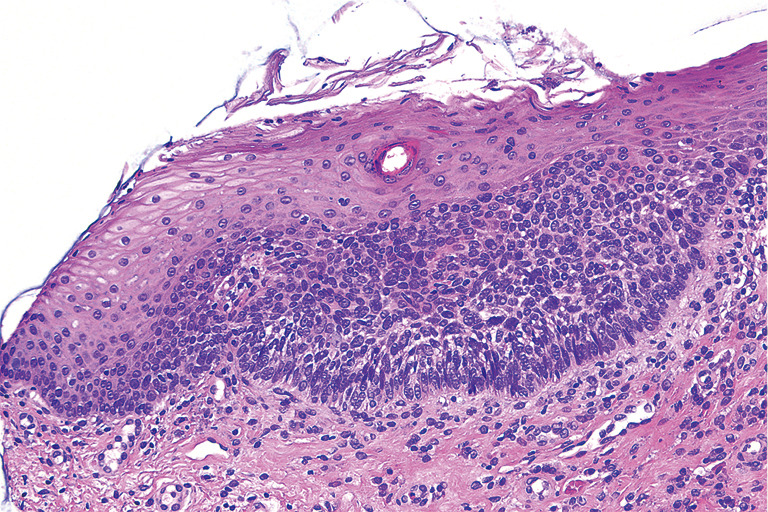

Background: Intraoral basal cell carcinoma (IOBCC) is an extremely rare cancer and is usually treated with surgical excision. However, the management of recurrent IOBCC not amenable to resection is unknown. We report a case of effective treatment of recurrent IOBCC with vismodegib with rapid and durable response following only 6 months of treatment.

Case description: A 60-year-old female with IOBCC was first diagnosed in August 2016 involving right buccal mucosa and right anterior hard palate. She subsequently underwent wide local excision with involved margins. Her first local recurrence occurred four and a half years after initial diagnosis and went on to have further surgical resection. Her second local recurrence occurred 2 years later, where further surgery and radiotherapy were not amenable. She was then treated with vismodegib 150 mg daily, delivered via her gastrotomy feeding tube and she achieved clinical complete response within 3 months of treatment. Following 6 months of treatment, due to progressive side effects, she ceased treatment. She remains on surveillance and disease-free on clinical examination and repeat biopsy for the past 2 years. To our knowledge, this is the first case of inoperable recurrent IOBCC treated with vismodegib, delivered via gastrotomy tube, leading to a durable complete response. The patient's tumour showed significant regression within 3 months of treatment initiation, with continued improvement over the following year. The rapid and durable response to vismodegib in this case is particularly noteworthy, considering the aggressive nature of recurrent IOBCC and the patient's prior treatment history. The effective administration of vismodegib through a gastrostomy feeding tube is an additional important clinical finding. This approach demonstrates the flexibility of vismodegib treatment and may be applicable to other patients facing feeding or medication administration challenges.